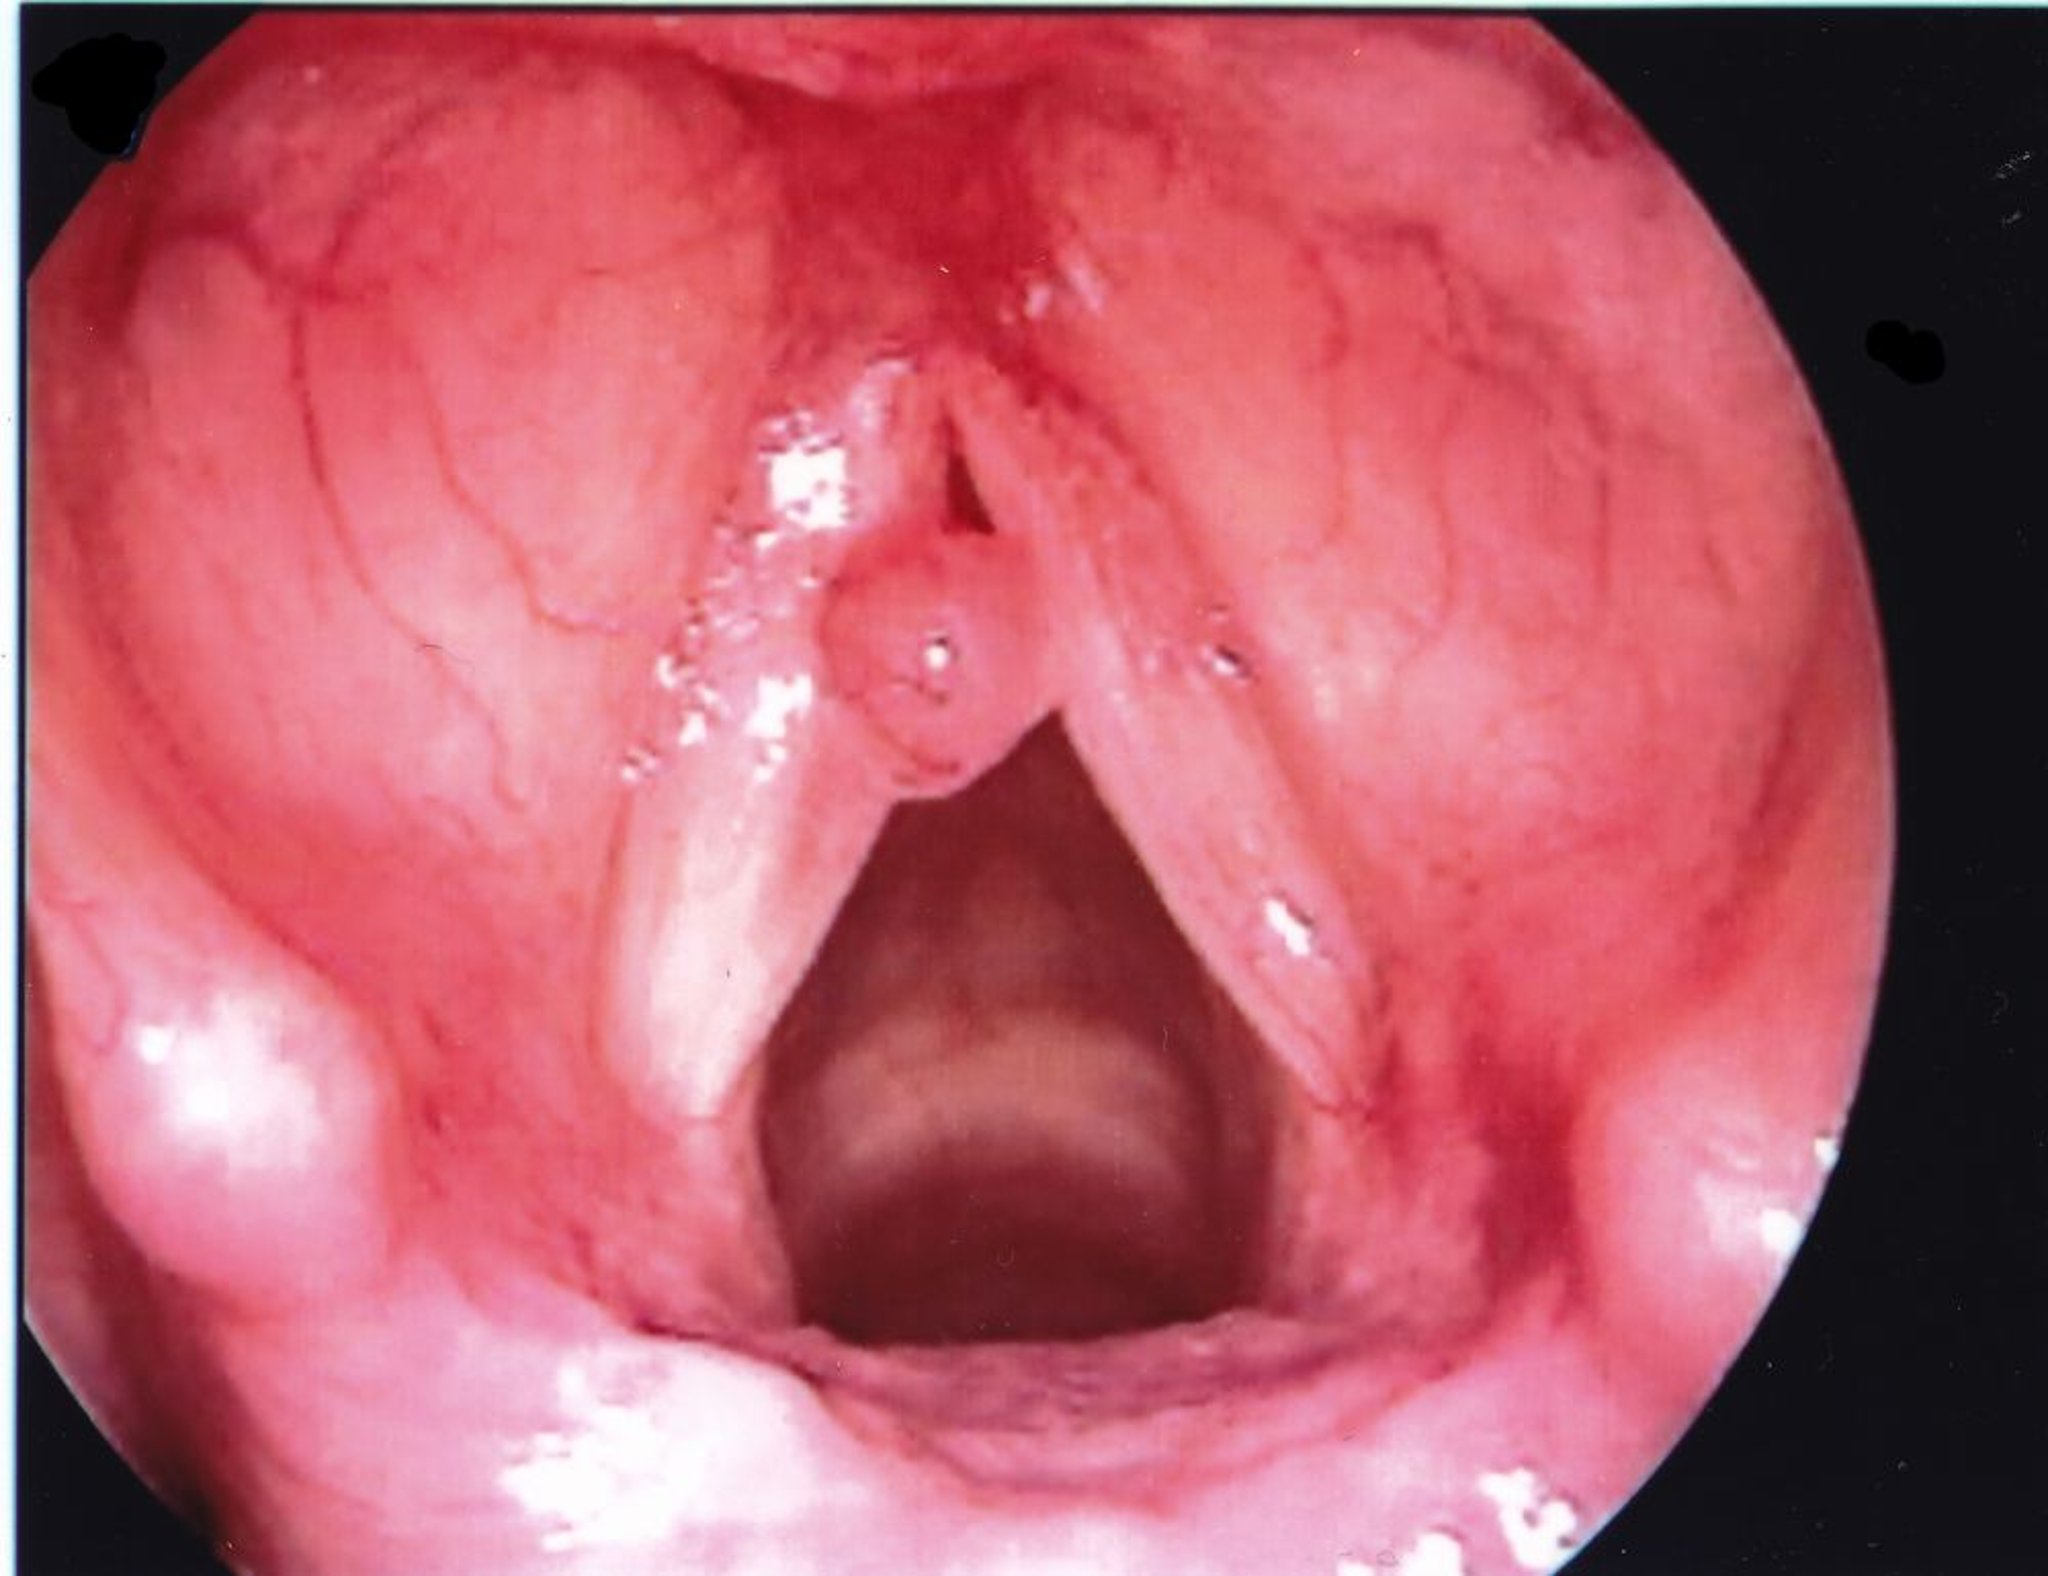

Polipo delle corde vocali

Un polipo alle corde vocali di solito appare unilaterale e più grande di un nodulo.

Immagine fornita da Eiji Yanagisawa, MD.